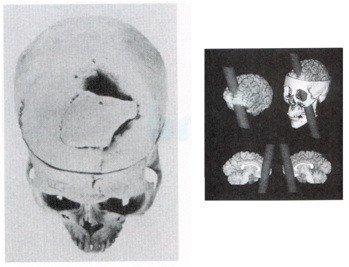

뇌와 감정의 관계와 관련된 유명한 일화의 주인공이다. 게이지는 미국의 어느 한 철도 공사 조직의 감독관이었다. 1843년 9월 13일, 25살의 게이지는 동료들과 함께 버몬트 주의 한 철도 공사에서 일하고 있었다. 구멍에 폭발물을 넣고 철 막대기로 구멍의 표면을 고르게 하기 위한 작업을 하던 중 실수로 주변 바위를 쳐 다이너마이트가 폭발하였고 그 폭발의 충격으로 철 막대기가 게이지의 왼쪽 뺨에서 오른쪽 머리 윗부분으로 뚫고 지나가버렸다. 그 결과, 그는 두개골의 상당 부분과 왼쪽 대뇌 전두엽 부분이 손상되는 심각한 상처를 입게 되었다.

게이지는 Dr. John Martyn Harlow에게 치료를 받아 다행히 죽을 고비는 넘겼지만 그의 머리에는 9cm 가 넘는 지름의 구멍이 생겨 있었다. 그가 죽을 것이라는 것은 어느 누구도 의심하지 않던 상황이었다. 그러나 사고 후, 몇 주동안 수많은 감염들이 생겨났지만 약 한 달이 지나자 그는 완벽하게 회복되었다. 그 후, 할로우 의사는 게이지의 가족과 몇 년동안 함께 지내며 게이지의 행동들을 관찰한 후 Recovery from the Passage of an Iron Bar Through the Head 라는 글을 발표했다.

할로우 의사가 발견한 흥미로운 점은 사고 전후로 게이지의 성격과 행동양상이 완전히 뒤바뀌었다는 것이었다. 마치 다른 사람이 된 것처럼 그의 변한 성격 때문에 그의 친구들은 그를 더 이상 게이지로 보지 않게 될 정도였다. 대뇌 전두엽 손상이 성격과 행동에 큰 변화를 준다는 피니스 게이지의 사건은 19세기 신경과학에 큰 논쟁을 불러 일으켰고 뇌의 특정 부위의 손상이 성격과 행동에 영향을 준다는 것을 처음으로 제시한 사건이 되었다